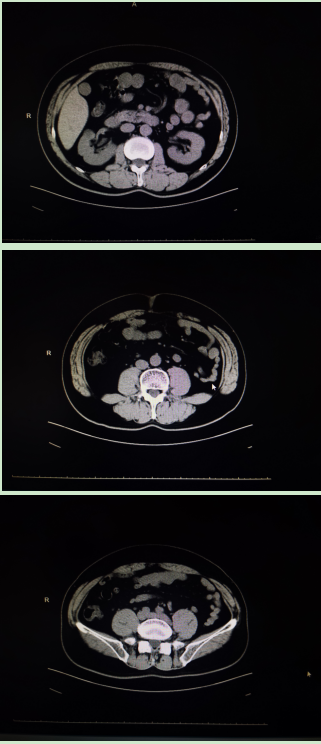

病例二

林先生,诊断:双侧输尿管上段结石并双肾积液。CT检查提示左输尿管上段结石约10*7mm,右输尿管上段结石约13*9mm。

行经尿道输尿管硕通镜下碎石清石术,碎石清石同步,手术高效无创,一次性把两侧结石处理干净,一次手术解决双侧泌尿系梗阻问题,避免造成肾功能衰竭。

手术前

手术后